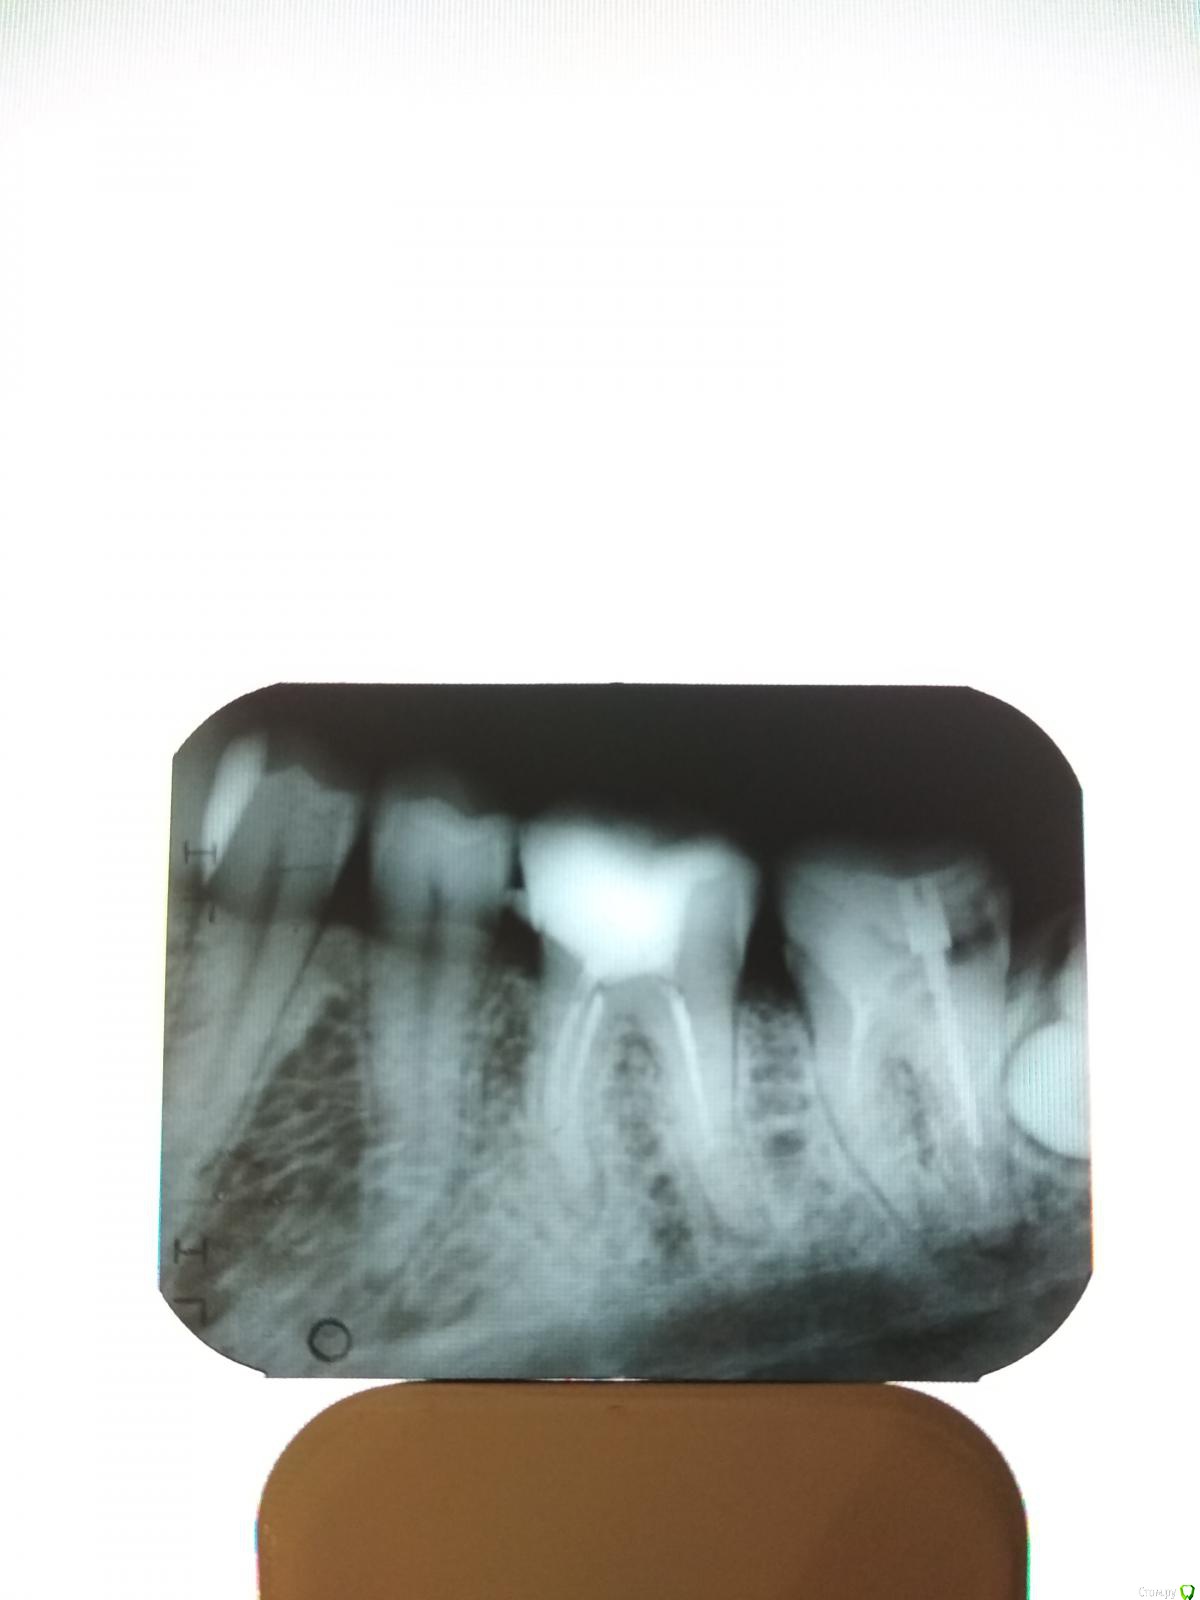

Анна.Л. Опубликовано 29 ноября, 2018 Поделиться Опубликовано 29 ноября, 2018 Добрый день! Подскажите каково состояние 4 и 5 зубов на снимке, есть ли на них кариозные полости. Спасибо Ссылка на комментарий

DmitrySH Опубликовано 29 ноября, 2018 Поделиться Опубликовано 29 ноября, 2018 на контактах небольшие полости в указанных зубах Ссылка на комментарий

DmitrySH Опубликовано 29 ноября, 2018 Поделиться Опубликовано 29 ноября, 2018 . На контактах это я понимаю где два зуба соприкасаются друг с другом? Спасибо. Верно, надо очно смотреть.У вас более интересные 6и 7 зубы Ссылка на комментарий

Анна.Л. Опубликовано 29 ноября, 2018 Автор Поделиться Опубликовано 29 ноября, 2018 Верно, надо очно смотреть.У вас более интересные 6и 7 зубыДа, снимок был сделан что бы определиться перепломбировать каналы или нет в 6. А 7 рекомендуют накрыть коронкой, но он разрушен, я так понимаю надо перепломбировать каналы ещё его подпирает 8-ка, переживаю что качественно не сделают и опять таки 8-ка. Как вы считаете стоит ли думать о накрытии коронкой. Ссылка на комментарий

DmitrySH Опубликовано 29 ноября, 2018 Поделиться Опубликовано 29 ноября, 2018 Да, снимок был сделан что бы определиться перепломбировать каналы или нет в 6. А 7 рекомендуют накрыть коронкой, но он разрушен, я так понимаю надо перепломбировать каналы ещё его подпирает 8-ка, переживаю что качественно не сделают и опять таки 8-ка. Как вы считаете стоит ли думать о накрытии коронкой.1. Убрать 8-ку2. Ревизия каналов 6 и 7 зубов3. Ортопедическое восстановление 6 и 7( если выявится что 7 очень сильно разрушен, тогда удаление и имплантация) Тут собственно и вариантов действий больше нет Ссылка на комментарий